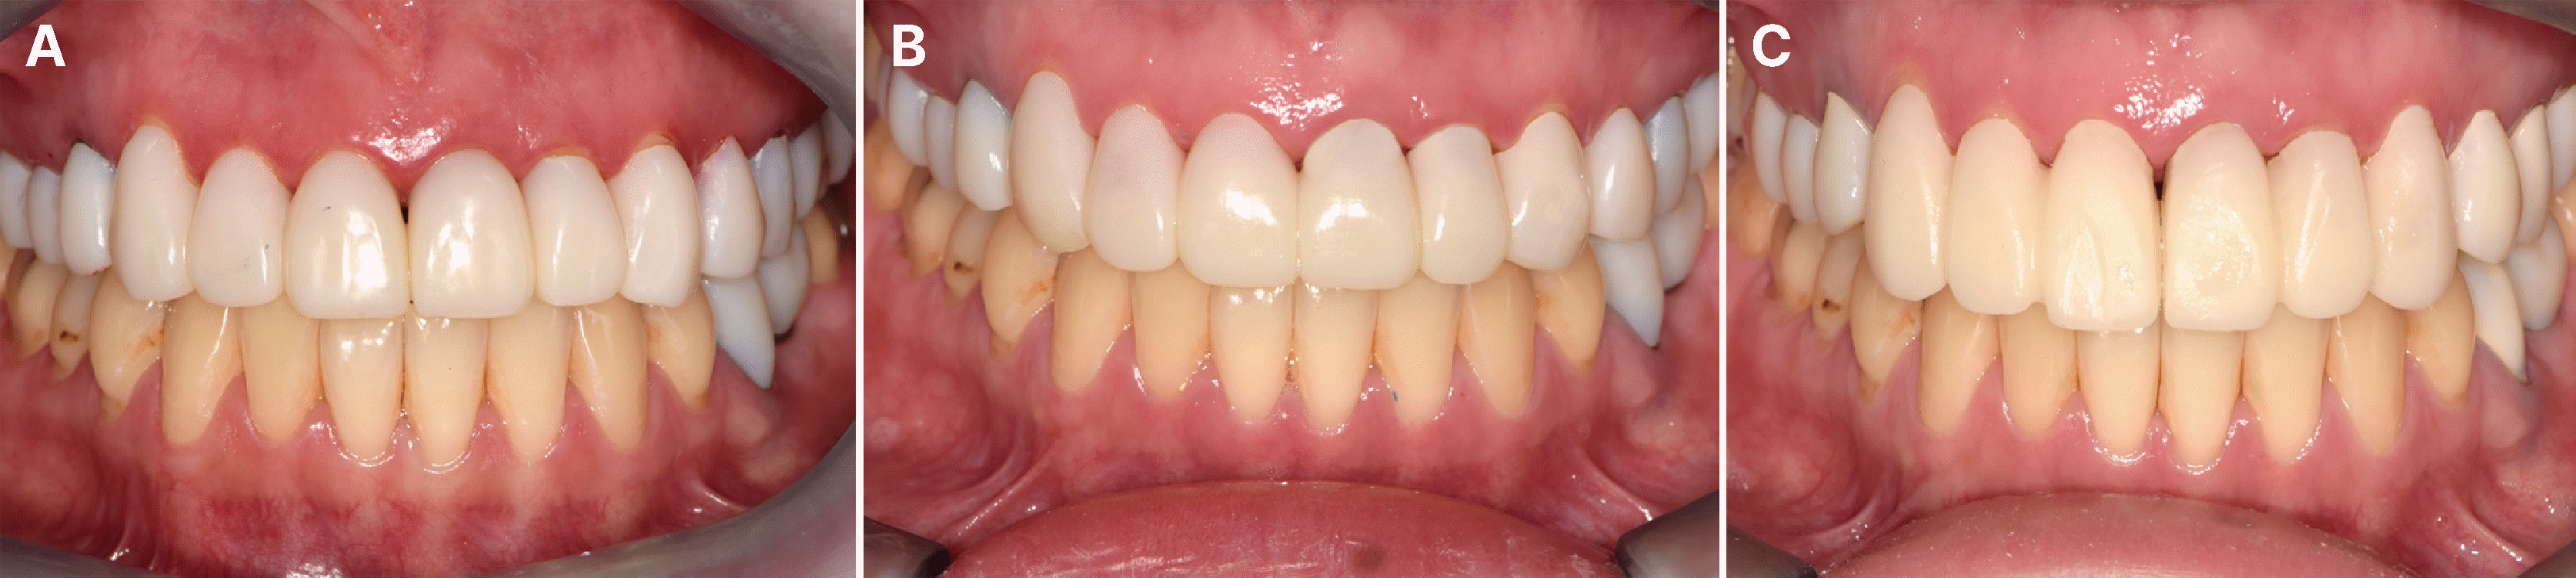

또한 서로 다른 세 가지 절단연 길이를 갖는 임시 수복물을 디자인하여 평가하였다. 각각 수직 피개가 0.5, 1.0, 1.5 mm인 상악 6전치 임시 수복물을 시적 후 평가했을 때, 1.0 mm 길이의 임시 수복물에서 가장 심미적인 교합 평면이 확인되어 이를 절단연 길이로 설정하였다(Fig. 12). 이를 고려한 최종 임시 수복물을 시적하였을 때, 정면에서 교합 평면의 기울어짐이 해소되었고, 적절한 미소선이 확인되었다(Fig. 13).

Fig. 12

Occlusal plane evaluation with different length of overlap. (A) 0.5 mm, (B) 1.0 mm, (C) 1.5 mm.